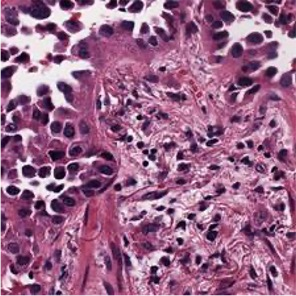

Multiple instance learning (MIL) is a powerful approach to classify whole slide images (WSIs) for diagnostic pathology. A fundamental challenge of MIL on WSI classification is to discover the \textit{critical instances} that trigger the bag label. However, previous methods are primarily designed under the independent and identical distribution hypothesis (\textit{i.i.d}), ignoring either the correlations between instances or heterogeneity of tumours. In this paper, we propose a novel multiplex-detection-based multiple instance learning (MDMIL) to tackle the issues above. Specifically, MDMIL is constructed by the internal query generation module (IQGM) and the multiplex detection module (MDM) and assisted by the memory-based contrastive loss during training. Firstly, IQGM gives the probability of instances and generates the internal query (IQ) for the subsequent MDM by aggregating highly reliable features after the distribution analysis. Secondly, the multiplex-detection cross-attention (MDCA) and multi-head self-attention (MHSA) in MDM cooperate to generate the final representations for the WSI. In this process, the IQ and trainable variational query (VQ) successfully build up the connections between instances and significantly improve the model's robustness toward heterogeneous tumours. At last, to further enforce constraints in the feature space and stabilize the training process, we adopt a memory-based contrastive loss, which is practicable for WSI classification even with a single sample as input in each iteration. We conduct experiments on three computational pathology datasets, e.g., CAMELYON16, TCGA-NSCLC, and TCGA-RCC datasets. The superior accuracy and AUC demonstrate the superiority of our proposed MDMIL over other state-of-the-art methods.